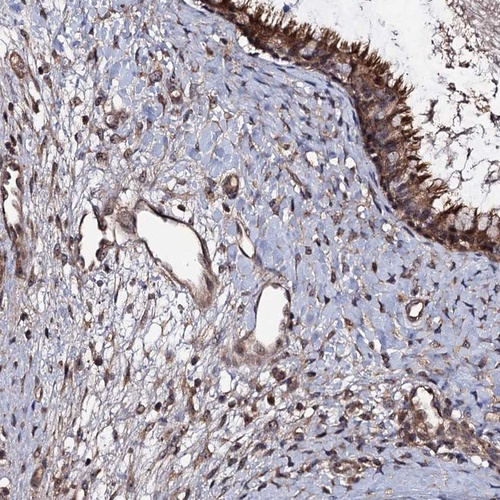

Immunohistochemical staining of human nasopharynx shows cytoplasmic positivity.